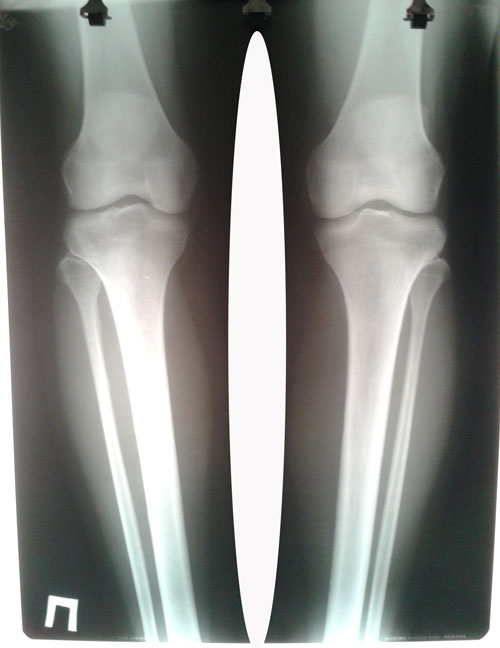

рентген до операции.

Исходник - 39 лет.

Дата операции 01.07.2016г.